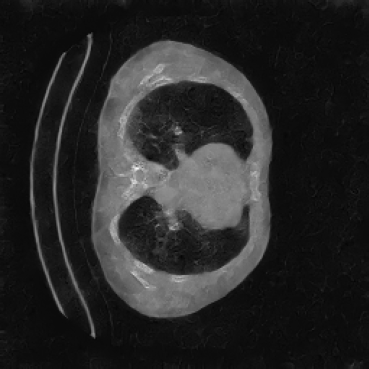

As shown in Figure 5, the generated slices exhibit high consistency across adjacent slices. The anatomical structures and semantic patterns are smoothly and coherently preserved between slices, indicating that our model is capable of generating 3D-consistent synthetic images rather than isolated 2D slices.

The hypothesis of this experiment is that if the synthetic images generated by our model resemble real medical images in distribution, a segmentation network trained on real data should yield similar performance on synthetic data. By comparing the segmentation results across real and synthetic images, we can quantitatively assess the structural fidelity and semantic consistency of the generated data. The results confirm that segmentation performance on synthetic images is highly comparable to that on real images, indicating that our model successfully captures anatomically relevant structures. This suggests that synthetic data are not only realistic but also potentially beneficial as an augmentation strategy to improve segmentation tasks. Visualizations of the segmentation output are presented in Figure 6.

Figure 8 further supports these findings: the images generated by Med-LSDM preserve spatial coherence across coronal and sagittal planes, whereas those from SegGuidedDiff show noticeable inconsistencies. These artifacts likely result from the 2D nature of SegGuidedDiff, which fails to account for 3D spatial relationships. In contrast, our model’s volumetric diffusion framework inherently preserves anatomical consistency, highlighting its advanta in synthesizing high-fidelity 3D medical images.